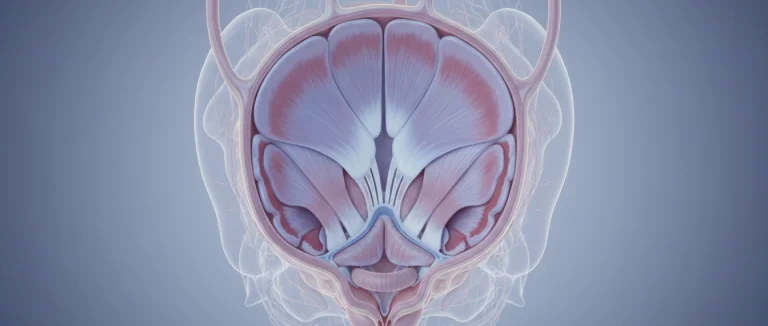

простата

Простата

простатическая уретра

Простатэктомия

Простатa